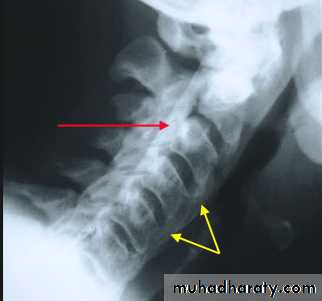

* Lower cervical and low lumbar spine are most comonly affected.* Osteophytes may encroach on neural foramina (best seen on oblique views).

*Vacuum phenomenon: gas (N2),is pathognomonic of the degenerative process.

* OA of the spine occurs in the apophyseal joints .

Cervical spondylosis